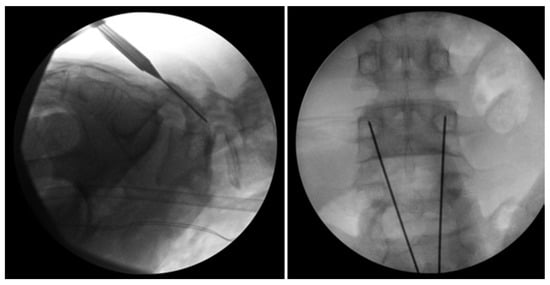

Levi Technique—Minimally Invasive Direct Pars Screw Placement